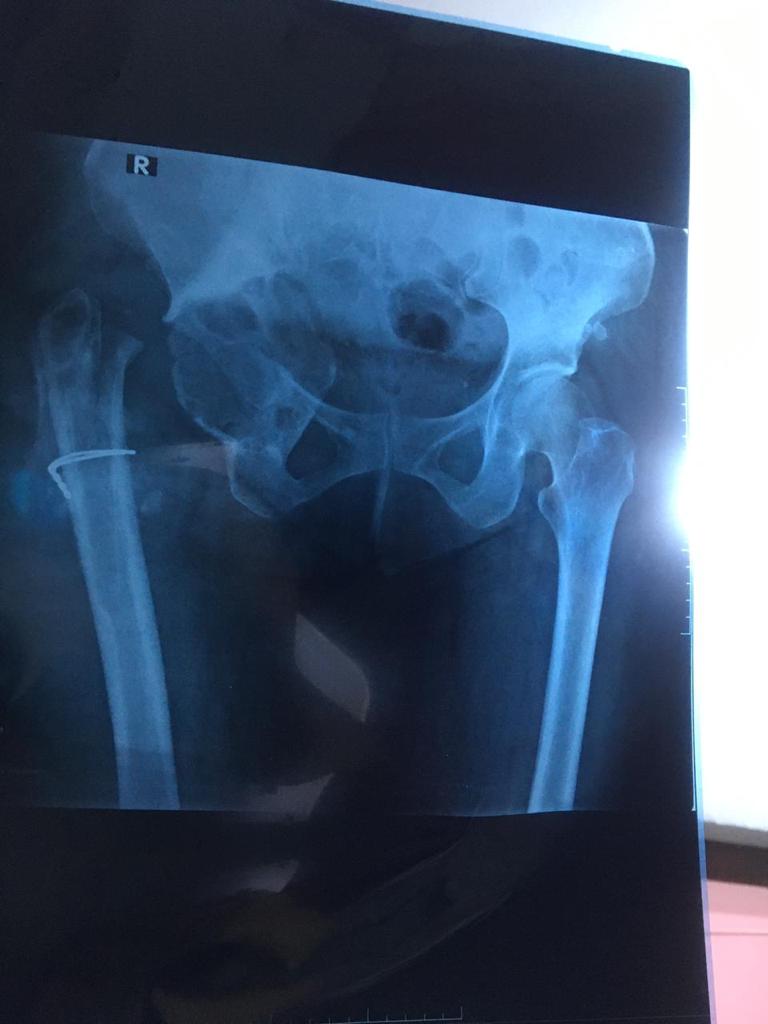

Revision Total Hip Arthroplasty

• Revision Total Hip Arthroplasty